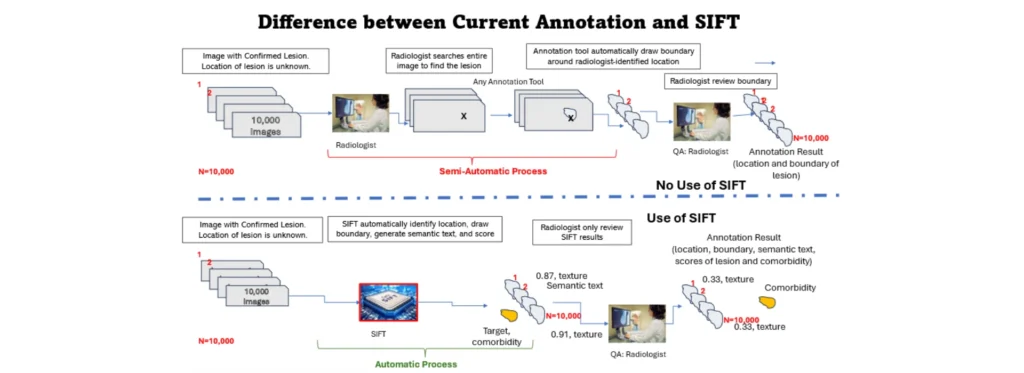

Caddie’s SIFT™ is the only fully automated annotation tool in the market capable of identifying 66 comorbidities on Chest X-ray and 44 abnormalities on Chest CT simultaneously. Designed specifically for chest X-ray and CT imaging, SIFT™ provides rapid, accurate, fine-grained image labeling and annotation to assist annotators in identifying abnormalities and their corresponding boundaries.

Providing Initial Type of Abnormalities SIFT™ can automatically detect and classify ROIs into specific types of abnormalities (“Predicted Disease”). It can predict 66 different types of abnormalities and recommend several options if the original prediction score is not high enough. Annotators can easily confirm or reject the type using SIFT’s interface.

- Compliance with Standards: SIFT™ complies with medical standards, with 90% of its disease lexicons matching MedDRA UMLS CUI coding and the remaining 10% aligning with Radiopaedia.

- Boundary Coordinates: SIFT™ can automatically draw ROI boundaries and predict location coordinates. Annotators can accept or edit the boundaries using the SIFT™ GUI.

- Batch Processing: SIFT™ can process a large number of CXRs to generate initial locations and boundaries without human intervention.

- Confidence Scores: SIFT™ generates confidence scores for each AI-specified ROI and predicted disease.

SIFT™ is capable of annotating comorbidity and seamlessly integrating with the radiologist workflow.

- Cost-Effective: Achieve 50-75% cost savings compared to traditional annotation methods, making it an economical choice for AI developers.

- Slow Manual Processes: Traditional annotation methods can be time-consuming, leading to delays in clinical trials. SIFT™ automates this process, significantly speeding up time to market.

- Human Fatigue: Radiologists often juggle multiple urgent tasks, introducing the risk of human error. SIFT™ reduces the burden on radiologists, minimizing fatigue-related mistakes.